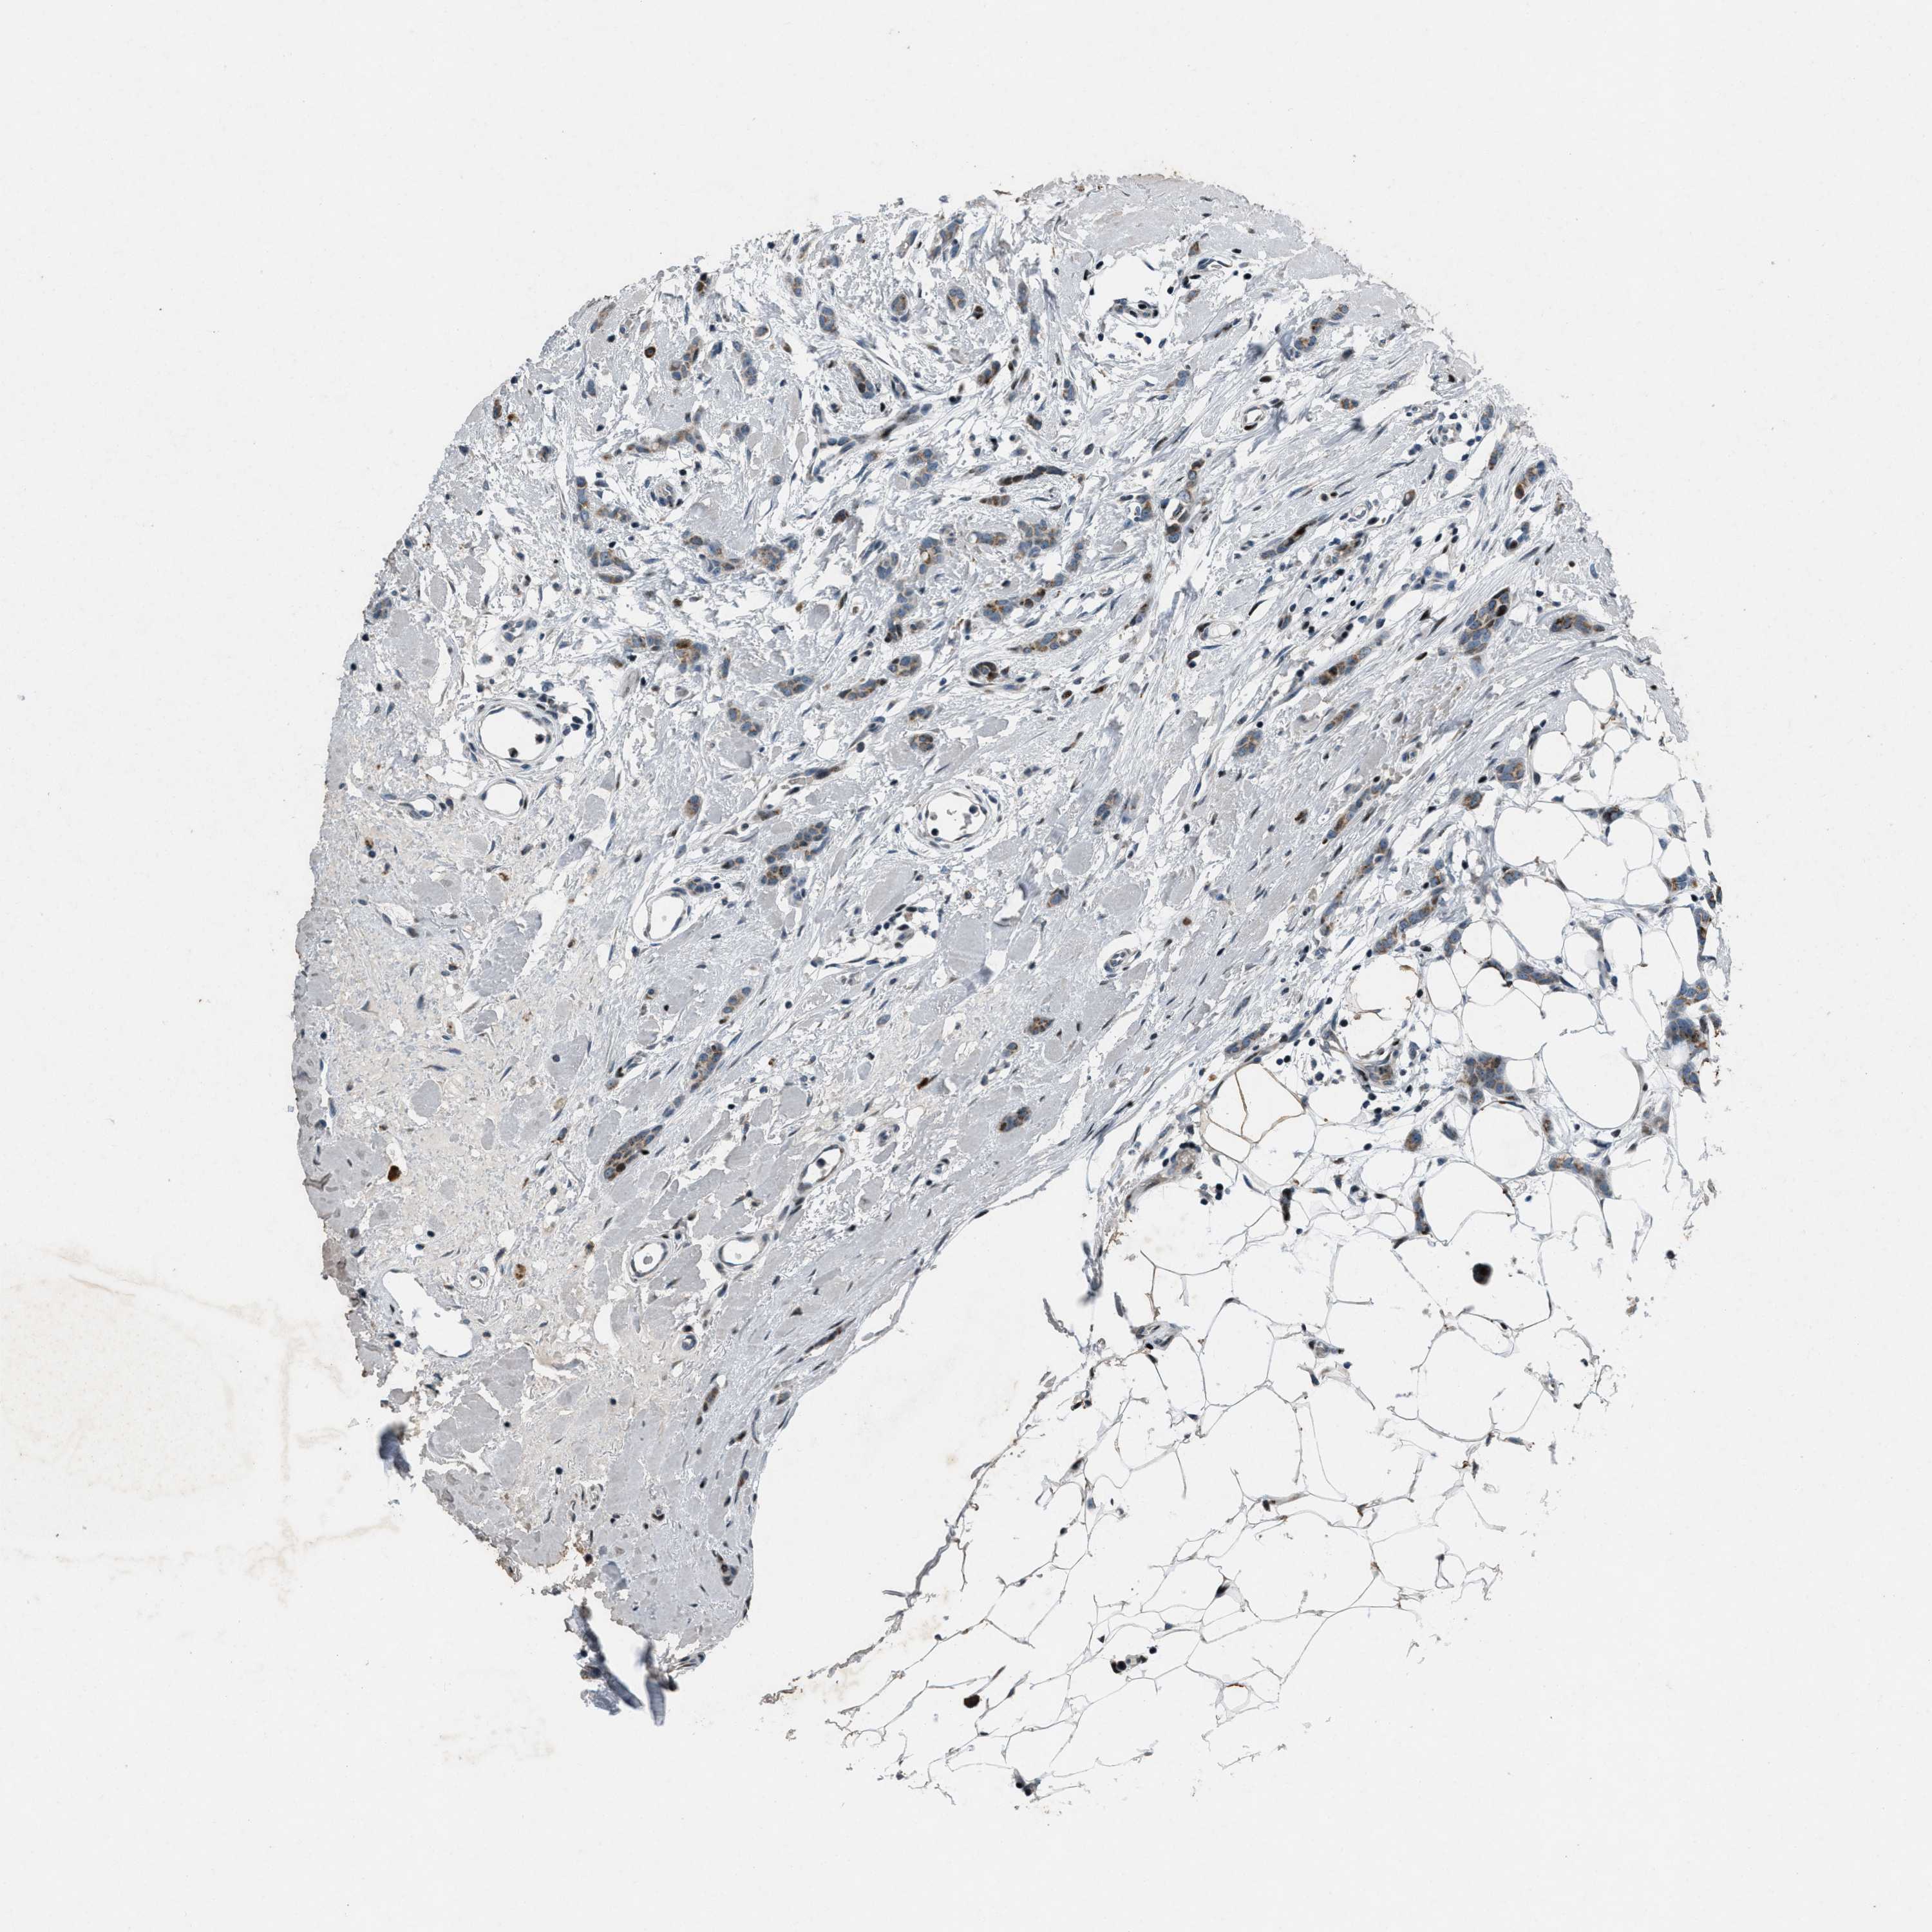

CANCER BREAST CANCER Show tissue menu

BRCA TCGA BRCA VALIDATION PROTEIN EXPRESSION